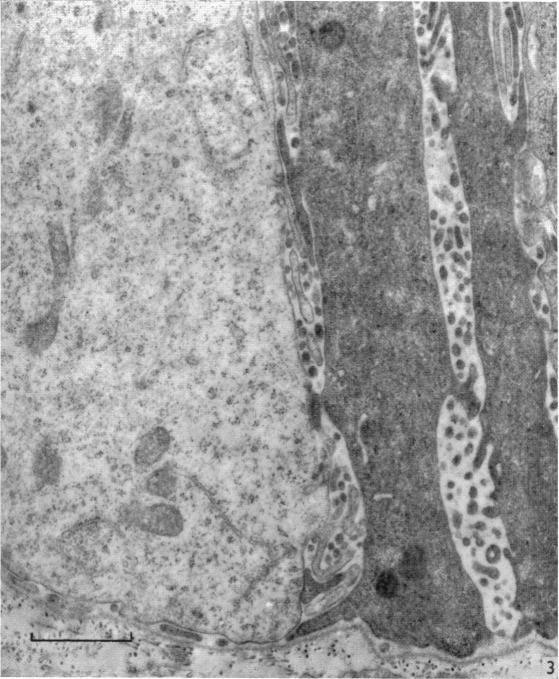

An electron microscopic study of developing gall bladder epithelium in the rabbit.

J Anat. 1966 Apr;100(Pt 2):245-59.

PMID:5954781

原文链接:https://pmc.ncbi.nlm.nih.gov/articles/PMC1270734/